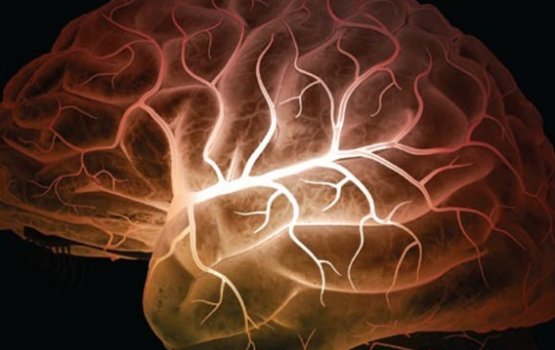

Однако последующий анализ ответных испытуемым сообщений показал, что выбранным ими людям они абсолютно не были симпатичны. Когда «подопытные» огорчались, снимки сканирования их мозга показали выброс опиоидов в эти моменты. Причем выброс веществ был зафиксирован именно в тех зонах головного мозга, которые участвуют в обработке болевых сигналов организма.

«Это первое исследование человеческого мозга, показавшее, что опиоидная система активируется при социальном отторжении. В общем было известно, что опиоиды вырабатываются при социальном стрессе и изоляции у животных, но где именно это происходит в мозгу человека, до сих пор не было известно», — пояснил ведущий автор научной статьи из Мичиганского университета Дэвид Сюй, сообщает РИА Новости.

Исследователи изучили и обратный эффект - когда испытуемым становилось известно, что они понравились тем, кого выбрали. И снова в эти моменты некоторые области мозга получали повышенное количество опиоидов.

Таким образом, учеными был сделан вывод о том, что опиоидные рецепторы, обеспечивающие анестезиологическую функцию организма человека, а также отвечающие за чувство удовольствия, работают в ответ на социальные отношения человека, связанные с его эмоциональными потрясениями, как положительными, так и отрицательными.